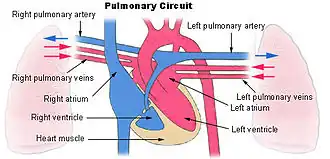

Малый (лёгочный) круг кровообращения

Структура

Начинается в правом желудочке, выбрасывающем венозную кровь в лёгочный ствол. Лёгочный ствол делится на правую и левую лёгочные артерии. Лёгочные артерии ветвятся на долевые, сегментарные и субсегментарные артерии. Субсегментарные артерии делятся на артериолы, распадающиеся на капилляры. Отток крови идет по венам, которые собираются в обратном порядке и в количестве четырёх штук впадают в левое предсердие, где заканчивается малый круг кровообращения. Кругооборот крови в малом круге кровообращения происходит за 4—5 секунд.

Функции

Основная задача малого круга — газообмен в лёгочных альвеолах и теплоотдача.